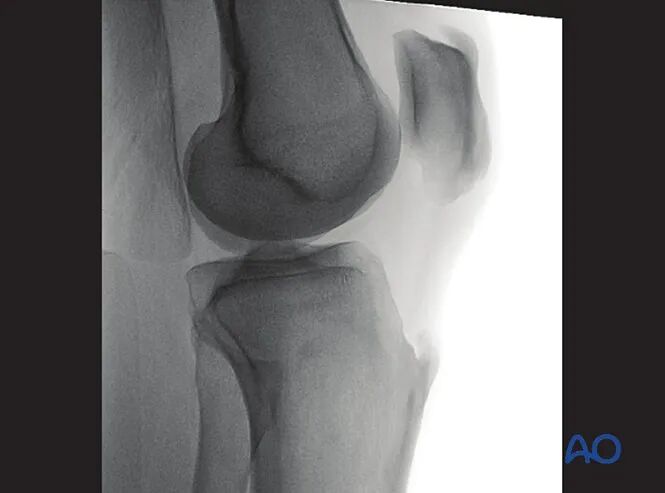

3. 胫骨近端侧位

最佳体位摆放要求

获取股骨远端标准侧位影像需满足:

●患侧下肢屈曲抬高膝关节;

●下肢保持中立旋转位。

最佳影像的验证标准

满足以下条件即为胫骨近端最佳侧位影像:

●射线束平行于胫骨关节面(或垂直于胫骨长轴);

●股骨内外髁的前、远端及后缘完全重叠;

●股骨内外髁居中显示于影像屏幕。

可识别的解剖标志与线条

胫骨近端侧位影像中可清晰识别的解剖标志与线条包括:

1.外侧胫骨平台(凸面线影)

2.内侧胫骨平台(凹面线影)

3.胫骨棘

4.胫骨结节

5.骨骺线瘢痕。

临床观察要点

该体位尤其适用于判断以下情况:

●内外侧胫骨平台复位不良;

●胫骨棘复位不良;

●胫骨平台相对于股骨的前后向半脱位(提示交叉韧带损伤);

●关节内植入物位置。